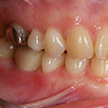

8. 施術前右側観

6番部の欠損です。両隣在歯は良い歯をしています。絶対削りたくありません。ましてやブリッジにするために、最後臼歯の咬頭関係を崩してまで削るのは、咬合を崩すことになります。単独インプラント適応です。22歳です。